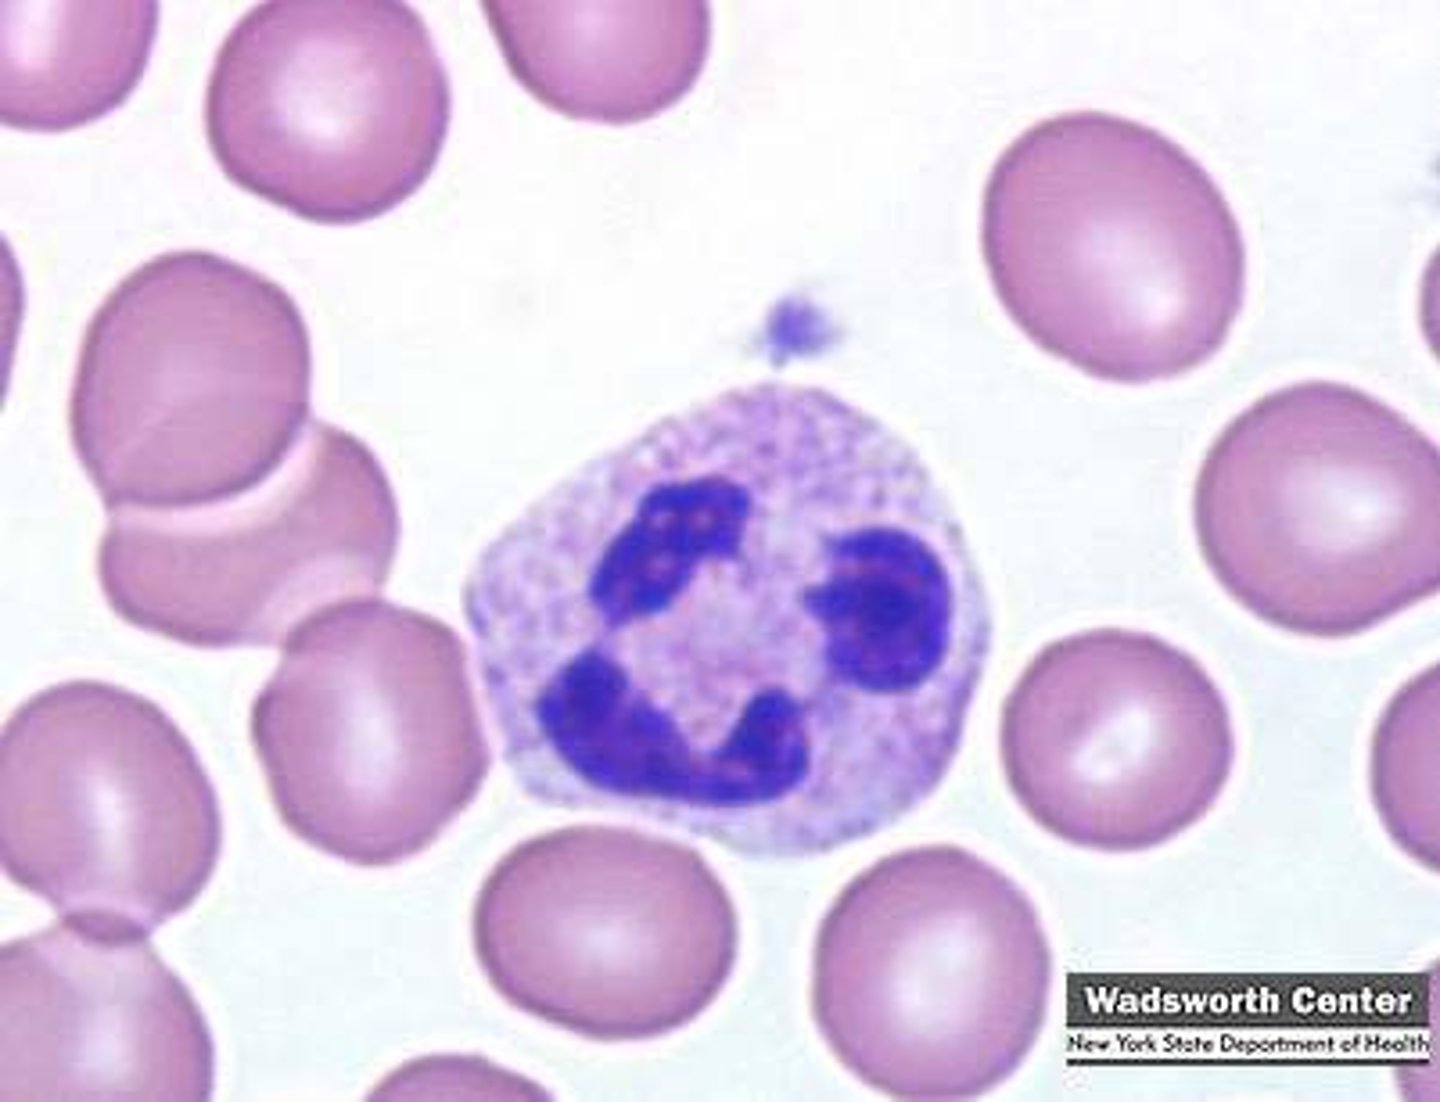

hyper-segmented neutrophils

MAMMAL

"old cell"

5+ lobes

toxic neutrophils

MAMMAL

1. increase basophilia in cytoplasm

2. dohle bodies

3. vacuolated/foamy cytoplasm

4. +/- increase in cell size

dohle bodies

MAMMAL